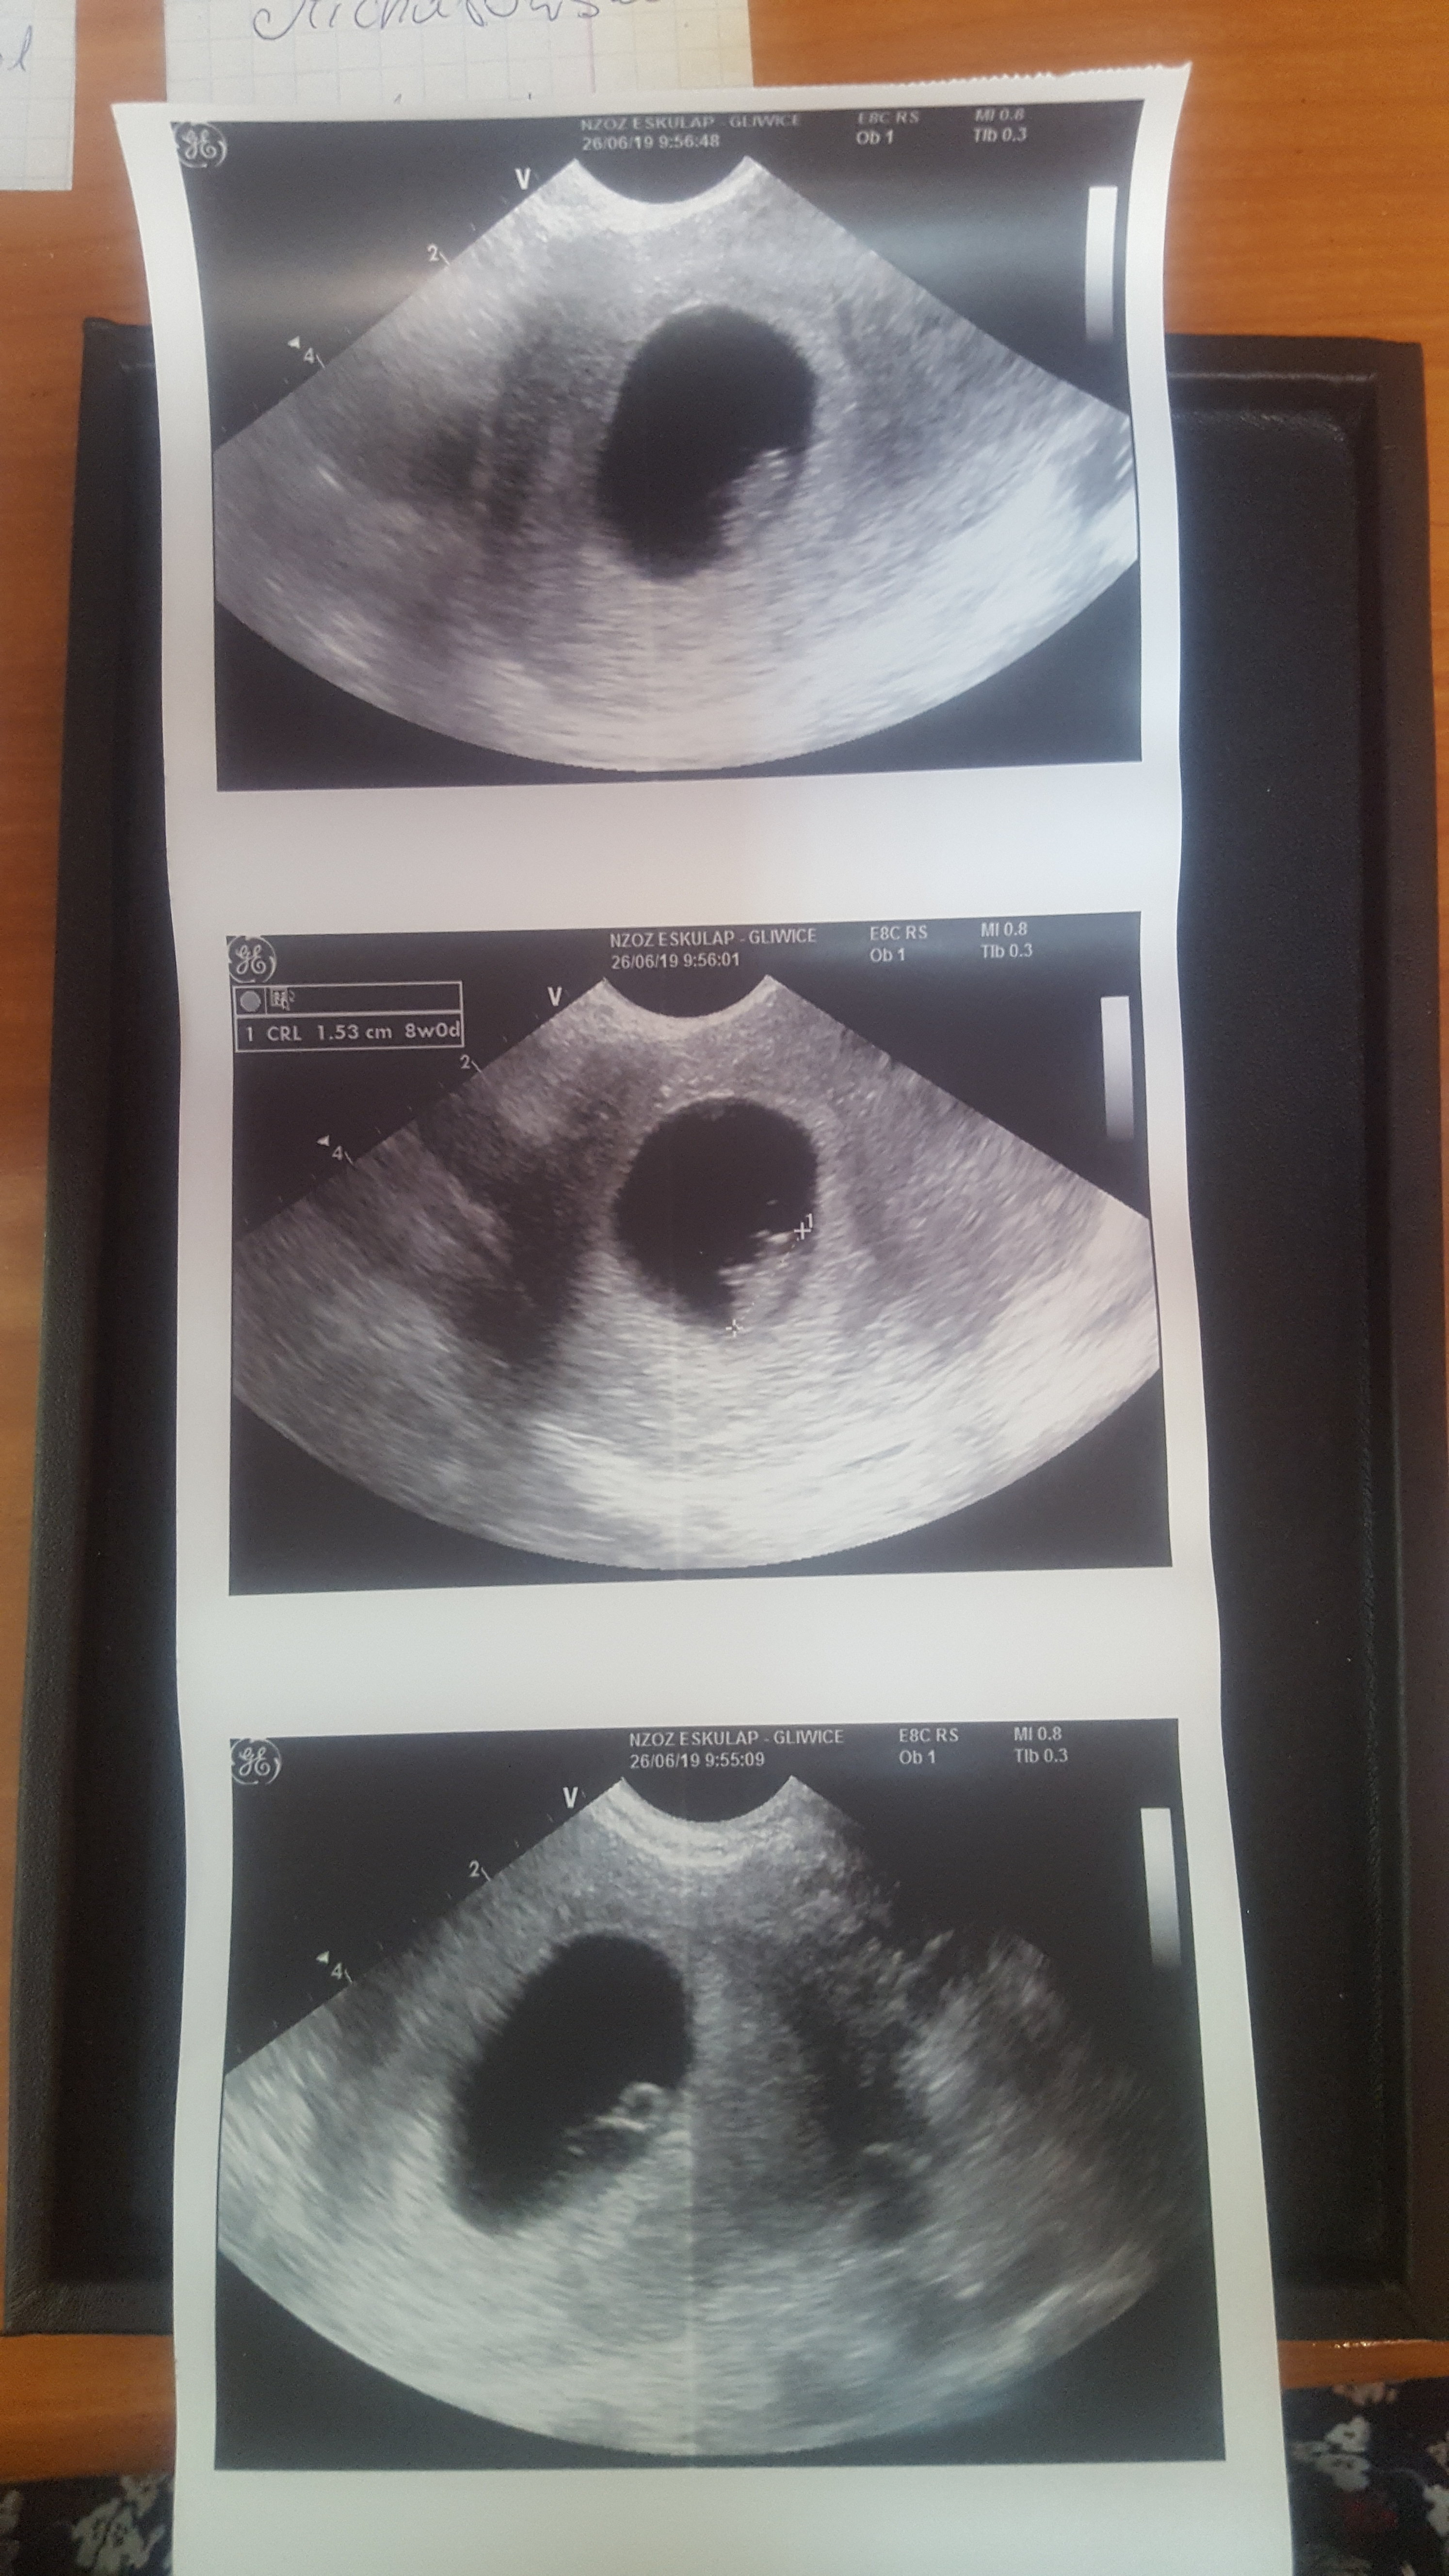

Hej :) ja po wizycie :) jest dzidzi, ma 15mm 8 tydzień :) było serduszko <3 widziałam jak bije w tym małym ciałku :) niesamowite uczucie. Teraz czekają mnie prenatalne ale niestety termin koliduje mi z wyjazdem:/ musze teraz pomyśleć jak to wszystko zgrać :)

Jestem bardzo szczęśliwa, mąż też! Byliśmy razem na wizycie

Termin mam na 2.02.2020